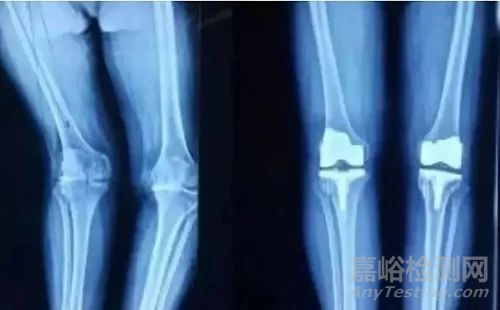

用于人工骨和人工關(guān)節(jié)的碳纖維

Invibio公司是醫(yī)療器械的知名供應(yīng)商,它所開發(fā)的短切碳纖維增強(qiáng)聚醚醚酮(PEEK),具有優(yōu)良的力學(xué)強(qiáng)度和抗拉蠕變性,可承載骨頭、血液及人體組織所需的負(fù)荷,與人體的相容性良好。這種人工骨的抗彎曲強(qiáng)度較其他生物材料制成的人工骨,更接近于真實(shí)的人骨,這對矯形醫(yī)學(xué)意義重大。用它制成的人工關(guān)節(jié)在活動連接處的耐磨性也比超高相對分子質(zhì)量聚乙烯及金屬制品要高。